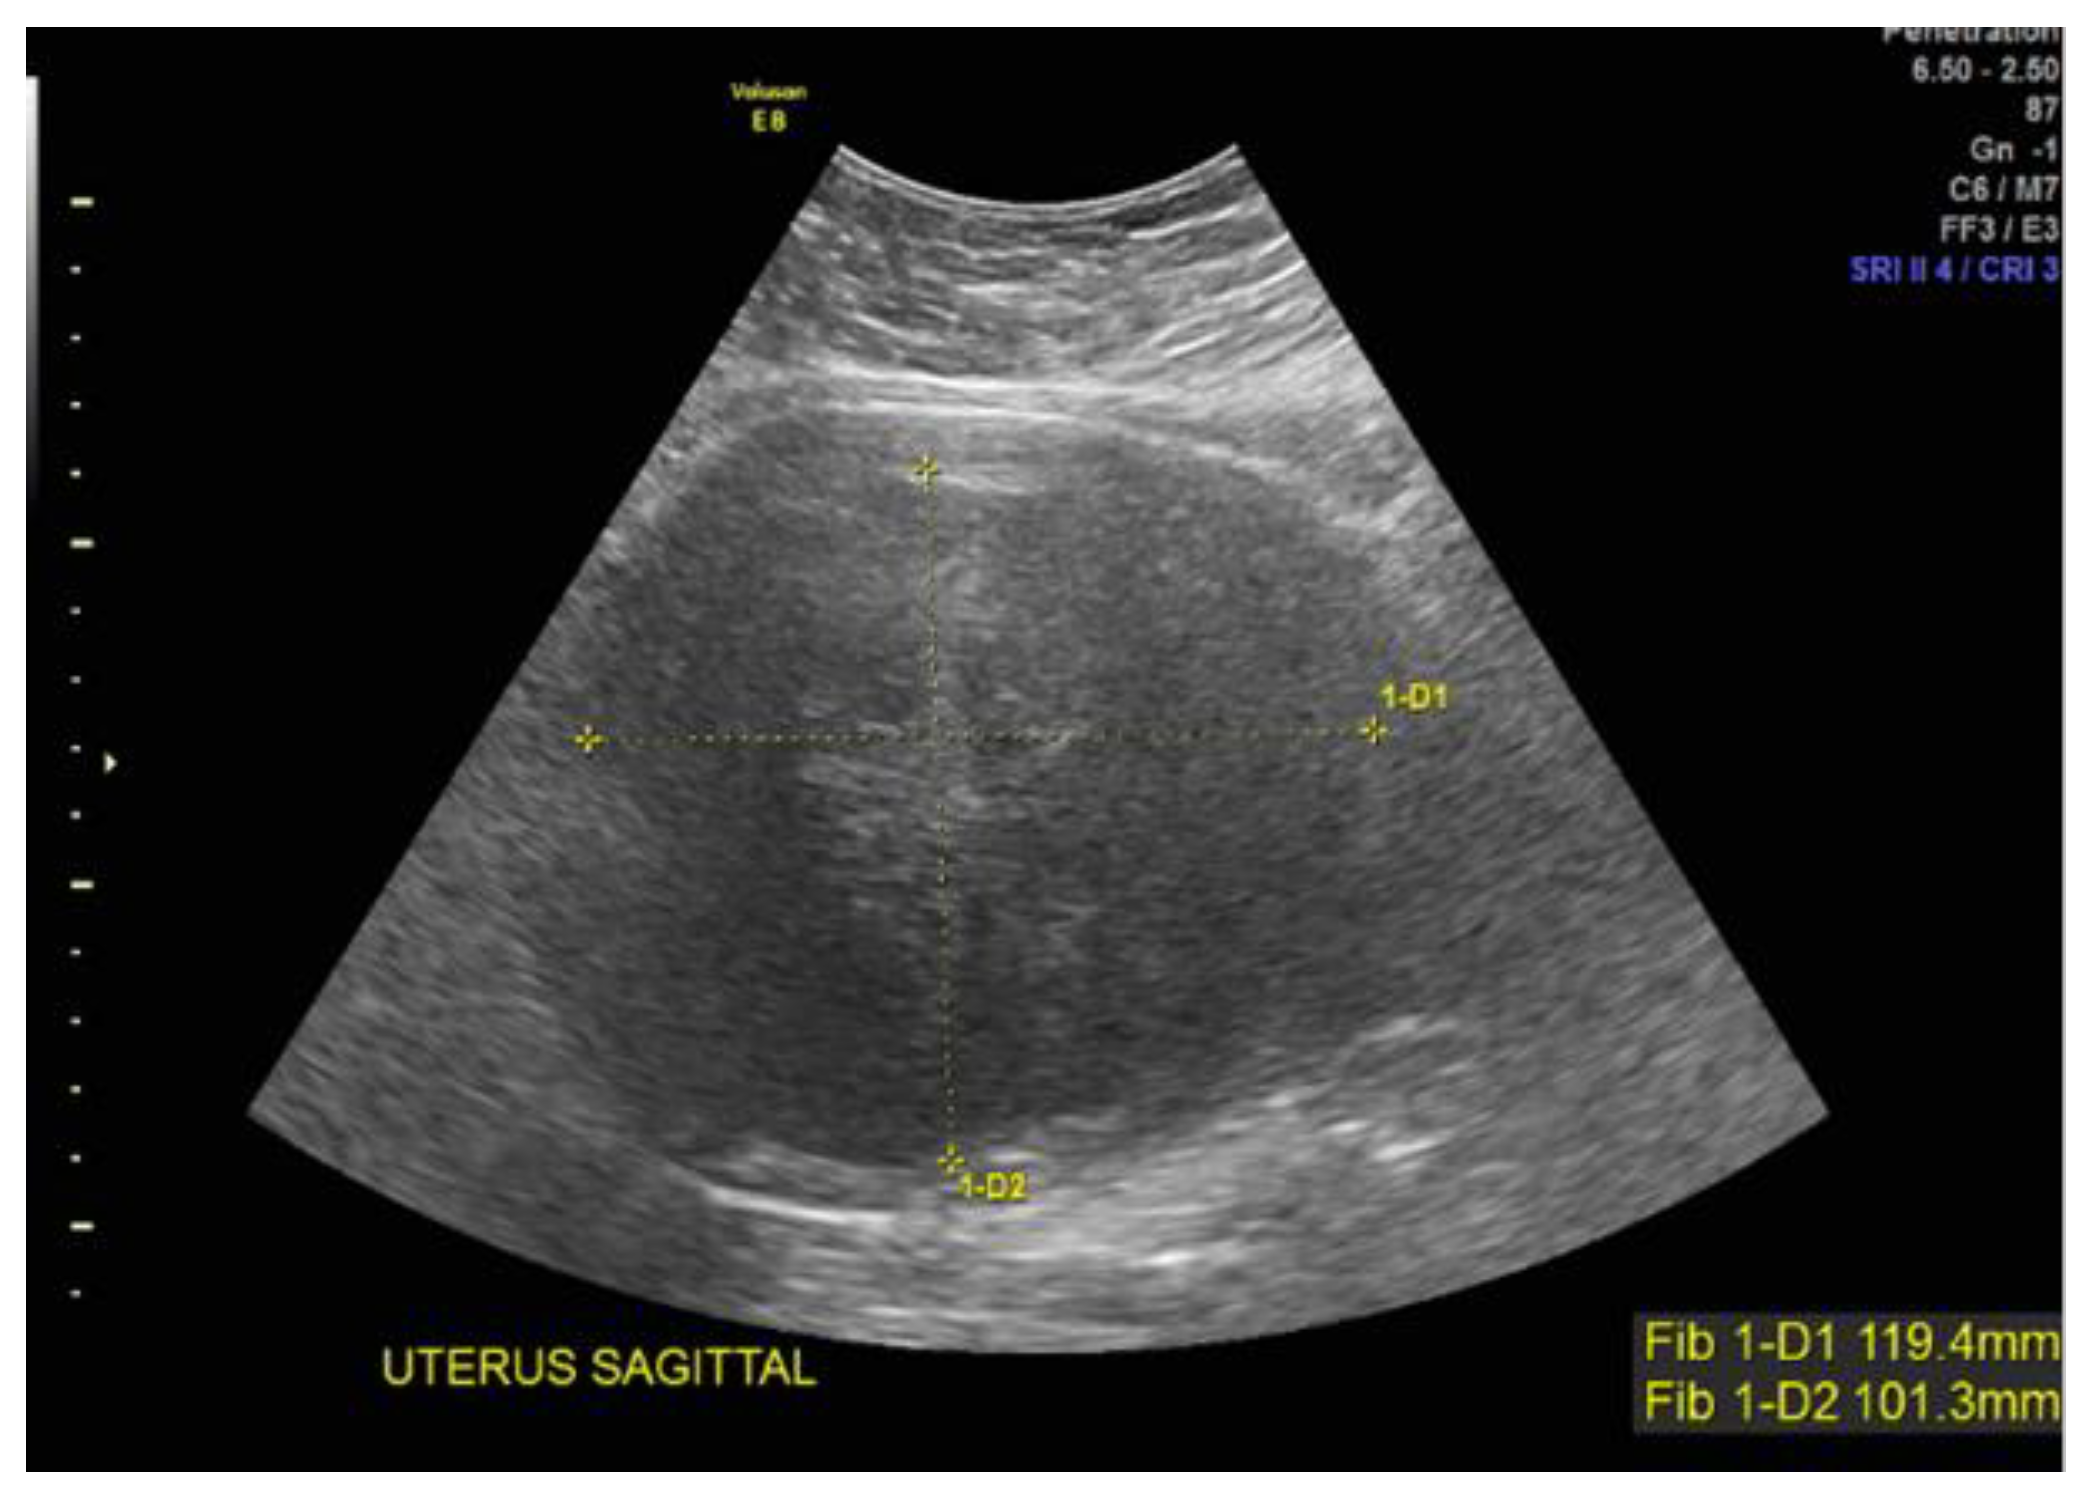

Case 4: A 38-year-old Black patient presented with pelvic pain and heavy menstrual bleeding due to a 10 cm subserosal fundal uterine fibroid (Figure 3). She underwent a robotic hysterectomy with bilateral salpingo-oophorectomy, which confirmed a leiomyoma with features of FH deficiency; germline genetic testing was negative for known pathogenic mutations.

Figure 3.

Subserous, fundal, homogeneous uterine fibroid.